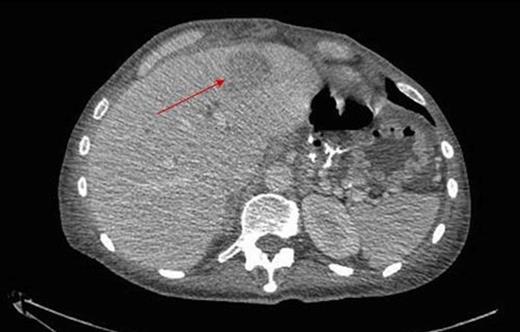

Due to clinical deterioration, a further CT was performed which demonstrated a large communicating collection filling the paracolic gutters and pelvis, with a multiloculated left lobe liver abscess, and a smaller abscess in the right lobe (figure 1). This was percutaneously drained and there was clinical improvement. The patient was discharged home.

Thrombus within the distal aorta shown by a filling defect (red arrow)

Extension into the left iliac artery shown by a filling defect (red arrow)